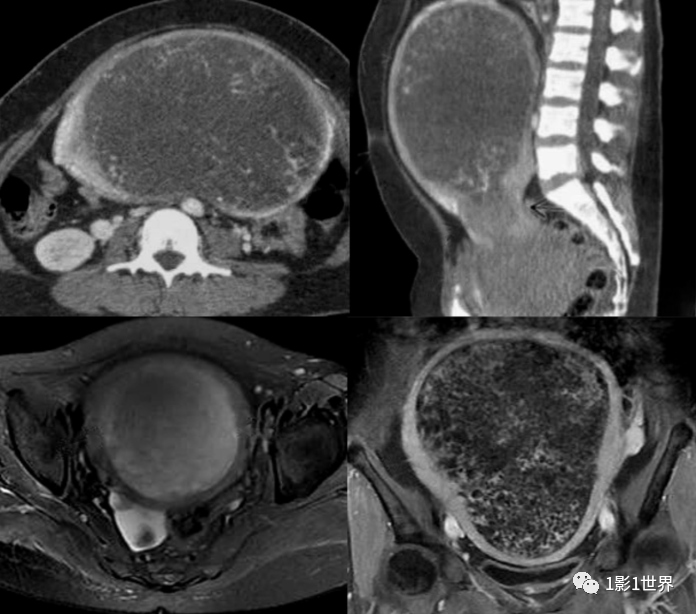

影像诊断

子宫体积增大

宫腔扩大

宫腔内多发小圆形囊状低密度病灶,聚集成团

子宫壁完整,厚薄不均

增大的卵巢常伴发黄素化囊肿

增强扫描:囊状病变分隔强化。

MRI检查

子宫体积增大,宫腔扩大

宫腔内多发T1WI低信号、T2WI高信号、DWI低信号的小囊样病变,有纤细分隔,呈蜂窝状或葡萄状,病变包膜完整。

伴有出血信号

子宫肌层受压变薄,结合带完整

增强扫描:表现为在扩张的子宫内膜腔内含有多个小囊腔样强化的异质组织,动脉期轻度不均匀强化,静脉期及延迟期渐进性网格状强化;宫旁见多发迂曲流空信号影,增强后可呈血管样强化

常合并卵巢黄素囊肿